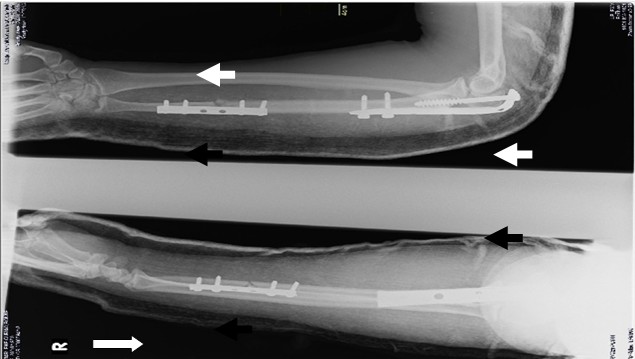

Al tener en cuenta todos los elementos anteriores y constituir una urgencia médica quirúrgica, se decide llevar a la paciente al quirófano, para tratamiento de tipo quirúrgico, donde se realizó reducción de la cabeza del radio, osteosíntesis del olecranon con placa semitubular de 4,5 milímetros y fijación del foco distal con placa semitubular de 3,5 milímetros. Luego, se colocó férula braquial por siete días para alivio del dolor (Figura 2).